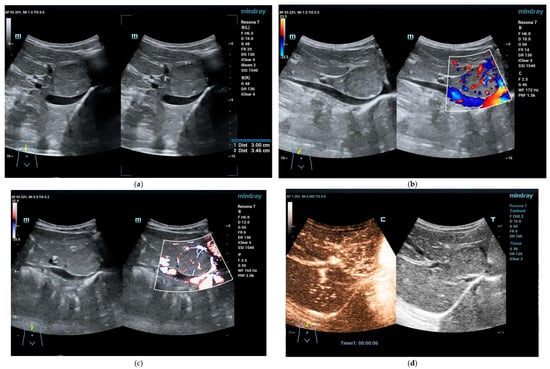

Focal Nodular Hyperplasia (FNH)

5. Focal Fatty Infiltration and Focal Fatty Sparing (Focal Fatty Lesions, FFL)

5.1. Focal Fatty Sparing (FFS)

5.2. Focal Fatty Infiltration (FFI)